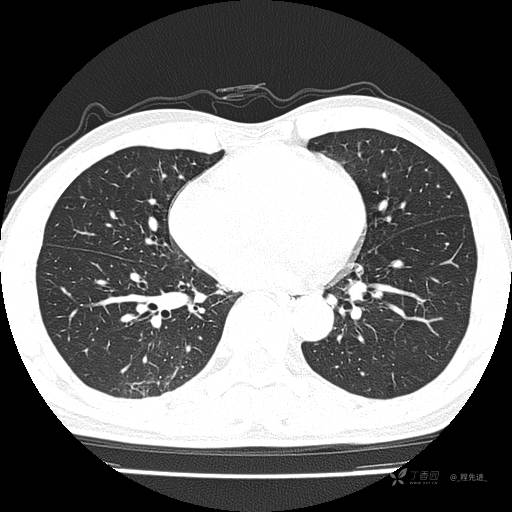

2月特别精彩病例|咳嗽、咳痰20余天,典型病例分享【结果已公布】

患者年龄:51岁

主诉:咳嗽、咳痰20余天

简要病史:20余天前开始出现咳嗽、咳痰症状,阵发性刺激性咳,白色粘痰,不易咳出,无发热,无咯血,无恶心、呕吐等不适,未诊治,咳嗽、咳痰症状持续存在。

体格检查:T:36.3 ℃ P:79 次/分 R:20 次/分 BP:128/64 mmHg,神志清楚,呼吸平稳,双肺呼吸音粗,右下肺闻及细湿性啰音。心率79次/分,节律整齐,各瓣膜听诊区未闻及病理性杂音。腹部未见异常,双下肢无水肿。

辅助检查:我院门诊胸部CT示:如下。心电图:窦性心律;正常心电图。